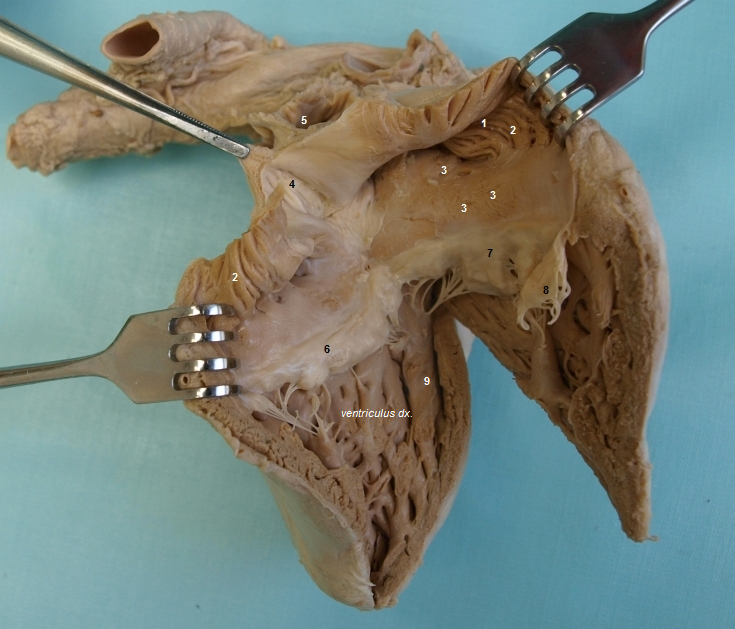

Navigace: Téma: Pohybový aparát > Kapitola: Srdce > Fotogalerie: Srdce > Snímek 7

Legenda: 1 - auricula dx., 2 - mm. pectinati, 3 - foramina venarum minimarum, 4 - fossa ovalis, 5 - ostium venae cavae sup., 6 - cuspis septalis (část valva atrioventricularis dx.), 7 - cuspis ant. (část valva atrioventricularis dx.), 8 - cuspis post. (část valva atrioventricularis dx.), 9 - trabecula septomarginalis